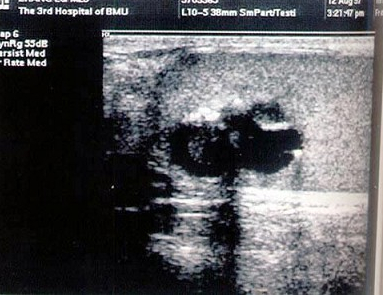

65、单项选择题

结合超声图像,该病例肾结石为哪一部位()